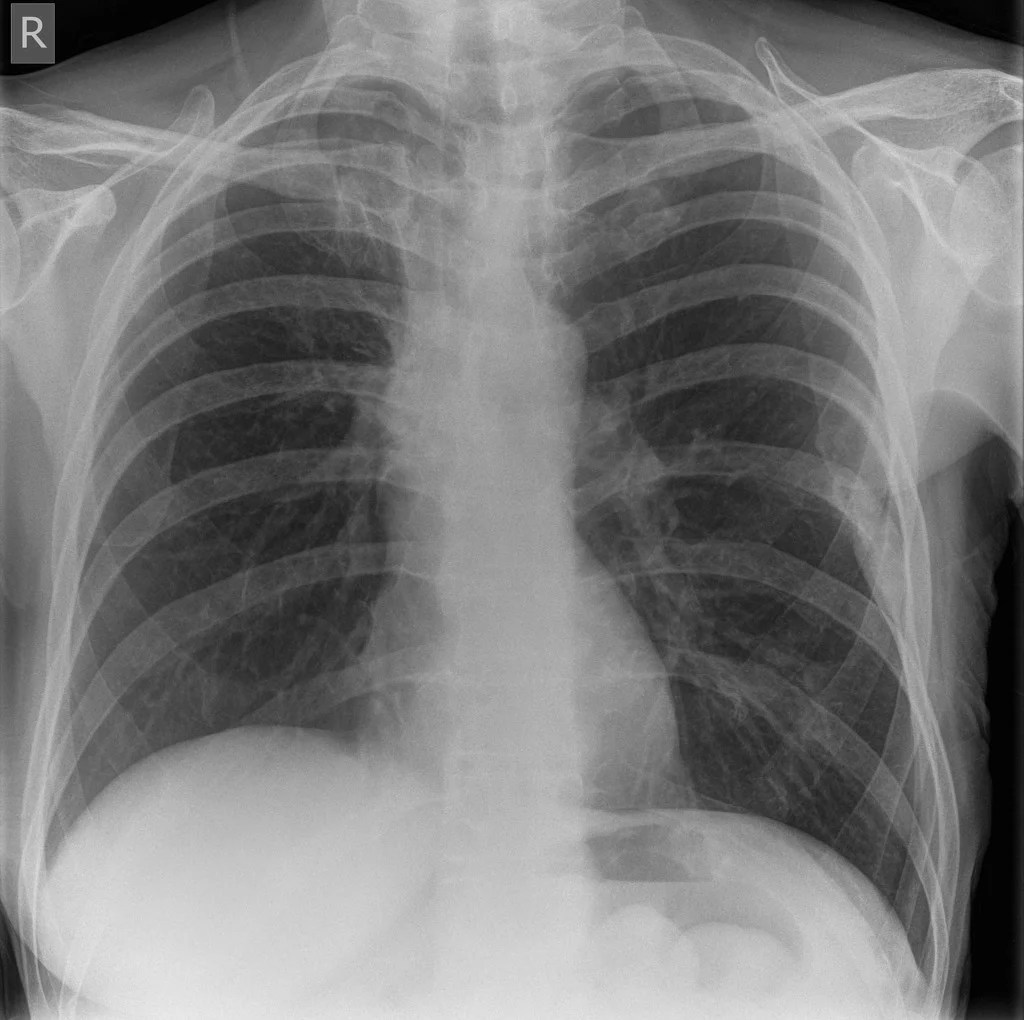

In an adult patient with a single bone lesion, metastasis is still the most likely diagnosis especially in a patient with known malignancy. In this way, your doctor can gather more information for diagnosis or treatment of. In fact, checks for tumors and overall bone density can be even more beneficial for long term health.

The bone scan has now added to the list of places that the cancer has decided to invade, now it includes one or two ribs. Ct, mri, and pet scans. But this test isnt needed if a chest ct scan (discussed below) has been done.

The pictures may also show missing bone or extra bone. Perhaps it is secondary to a medication that you may be taking (especially if you are taking an aromatase inhibitor). Lung cancer can spread to other ares of the lungs, lymph nodes, the.